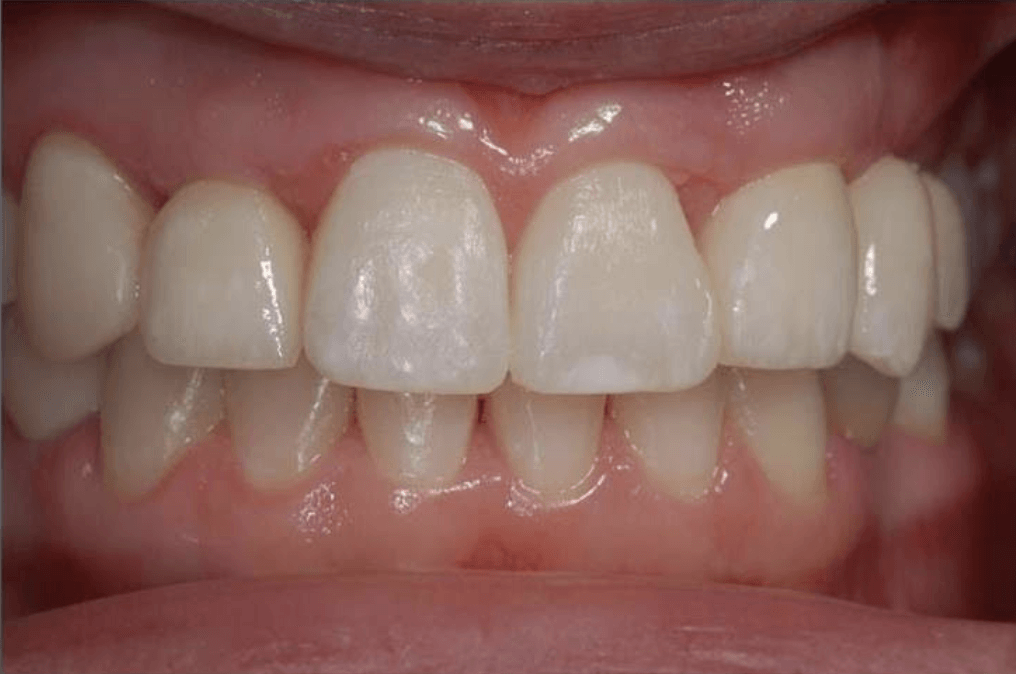

Porcelain Crowns

This patient was unhappy with the short length and discolouration of her teeth. We did a wax up study to evaluate the ideal size and length for her teeth. We then proceeded with six anterior porcelain crowns.